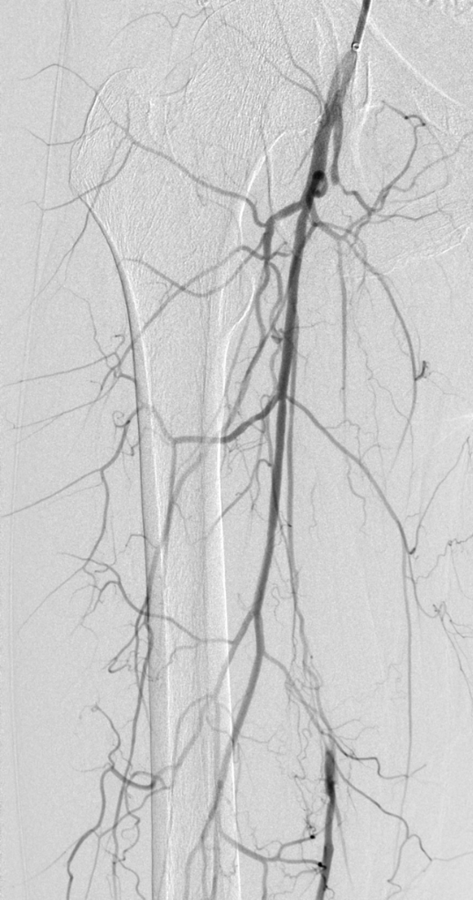

Abb. 1: Aortoiliakale Okklusion durch eine besondere Variante der PAVK, das Leriche-Syndrom. Mit der endovaskulären Behandlung gelang die Wiedereröffnung der Gefäße (davor). Abb. 1: Aortoiliakale Okklusion durch eine besondere Variante der PAVK, das Leriche-Syndrom. Mit der endovaskulären Behandlung gelang die Wiedereröffnung der Gefäße (davor). © Krankenberg H. Hamburger Ärzteblatt 2020; 74: 13-16 © Hamburger Ärzteverlag, Hamburg